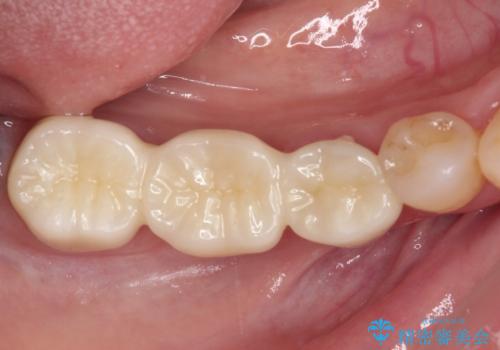

![[ 欠損補綴 ] ブリッジとインプラントの症例 治療後](https://seimitsushinbi.jp/wp/wp-content/uploads/2021/10/82c7cc111177152f4f990e0f169487f7-500x350.jpg?v=1634192579)

![[ 歯牙破折 ] 違和感のある大臼歯 ブリッジ治療の症例 治療後](https://seimitsushinbi.jp/wp/wp-content/uploads/2021/08/2e4ccba27e1ea02fdacf49749694bbb1-500x350.jpg?v=1629711051)